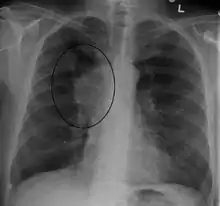

The main techniques of diagnosing SVCS are with chest X-rays (CXR), CT scans, transbronchial needle aspiration at bronchoscopy and mediastinoscopy.[6] CXRs often provide the ability to show mediastinal widening and may show the presenting primary cause of SVCS.[6] However, 16% of people with SVC syndrome have a normal chest X-ray. CT scans should be contrast enhanced and be taken on the neck, chest, lower abdomen, and pelvis.[6] They may also show the underlying cause and the extent to which the disease has progressed.[6]